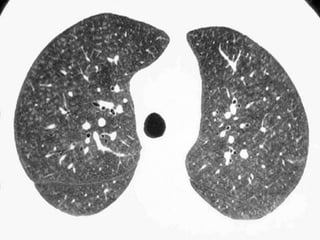

Lymphangioleiomyomatosis

(LAM)

HRCT Morphology

Thin-walled cysts (2mm - 5cm)

Uniform in size / rarely confluent

Homogeneous distribution

Chylous pleural effusion

Lymphadenopathy

in young women